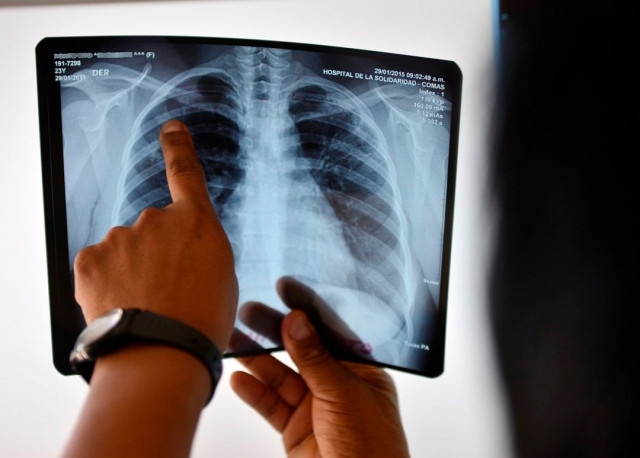

Tuberculosis (TB) continues to cast a long and deadly shadow across the globe, where Pakistan stands among the countries most affected by the disease.

TB claimed over 1.25 million lives worldwide by 2023, with 8.2 m new cases reported despite being both preventable and hardenable.

For Pakistan, the numbers are especially sober. Over 686,000 Pakistanis, including 81,000 children, developed TB last year. Estimated 47,000 lives were lost to the disease, many of them due to late diagnosis and lack of access to treatment. Experts say that overcrowding, poverty and weak health infrastructure are some of the conditions where TB thrives.

What makes it particularly dangerous is its ability to spread silently. The infected individuals remain asymptomatic for months and unconsciously pass on the disease. While first-line treatment can cure most TB cases, the increasing number of drug-resistant TB cases presents a serious threat of public health.